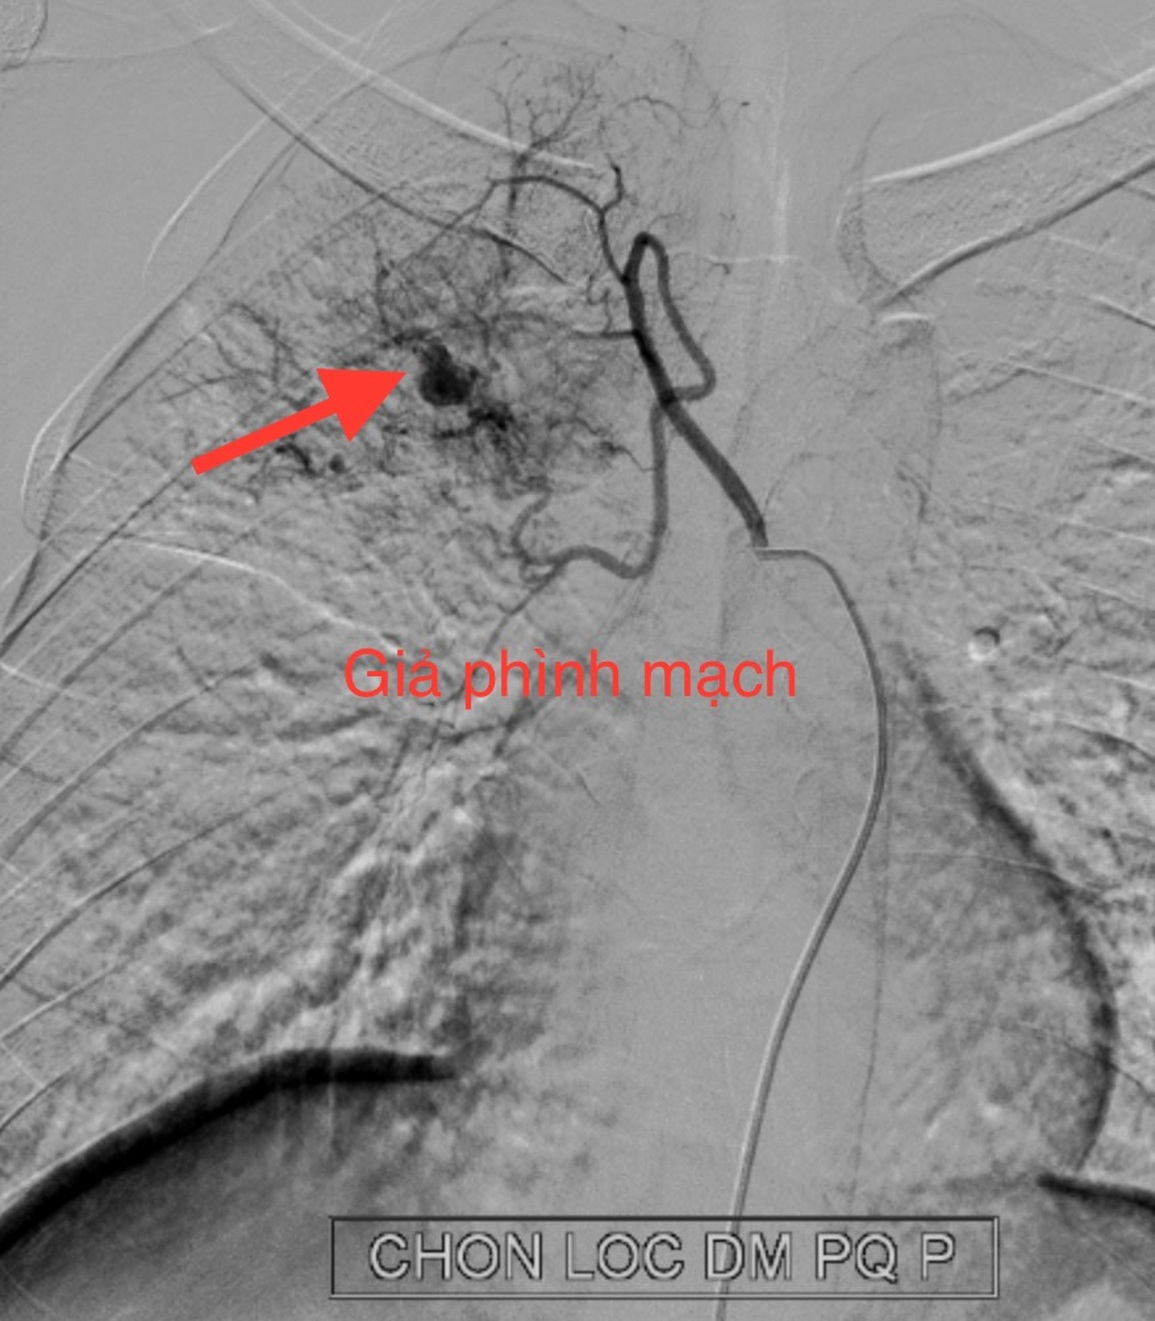

Tại đây, các bác sĩ phát hiện ổ giả phình lớn động mạch phế quản phải trong hang lao của bệnh nhân. Đây chính là nguyên nhân khiến bệnh nhân khi mắc Covid-19 bị ho máu ồ ạt. Bệnh nhân sau đó được chuyển về Bệnh viện Hữu nghị Việt Đức để can thiệp nội mạch cầm máu.

TS.BS Lê Thanh Dũng - Trưởng khoa Chẩn đoán hình ảnh, Bệnh viện Hữu nghị Việt Đức cho biết: "Ngay sau khi tiếp nhận thông tin bệnh nhân, chúng tôi đã ngay lập tức hội chẩn và đưa ra phương án can thiệp, kích hoạt quy trình điều trị cho bệnh nhân nhiễm Covid -19. Quá trình xử trí diễn ra rất khẩn trương, vì bệnh nhân có thể chảy máu tái phát và đe dọa tính mạng bất kì lúc nào. Thật may mắn, ca can thiệp đã diễn ra suôn sẻ, thuận lợi và không có bất kỳ biến chứng nào".

TS Dũng cho biết, ho máu do giãn động mạch phế quản là biến chứng nặng, có tỉ lệ tái phát cao. Nếu không được điều trị kịp thời, người bệnh có thể tử vong do suy hô hấp hoặc sốc mất máu. Vì vậy, các bác sĩ khuyến cáo, nếu bị ho ra máu, người bệnh cần đến ngay cơ sở y tế để khám, phát hiện nguyên nhân và điều trị kịp thời. Nút mạch cầm máu cấp cứu là phương pháp xâm lấn tối thiểu, an toàn, hiệu quả, tân tiến.